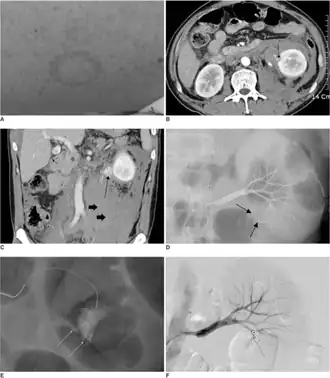

A man with hemorrhagic fever with renal syndrome complicated by bleeding around the kidney. A. Physical examination on admission reveals petechial rashes on the whole body. B. The contrast enhanced CT scan obtained on admission reveals active extravasation of contrast media (arrow) in the inferior portion of the left kidney and perirenal hematoma. C. The coronal reformatted image also shows active extravasation of contrast media at the inferior portion of the left kidney (arrow) with massive perirenal hematoma extending into the pelvic cavity (short arrows).D,E. Selective left renal arteriography (D) and superselective renal arteriography (E) show active extravasation of contrast media from ruptured branches of the inferior division of the renal artery (arrows). There is no hypervascular mass or arteriovenous malformation. F. Selective left renal arteriography performed after superselective embolization with microcoils demonstrates no more extravasation of contrast media.